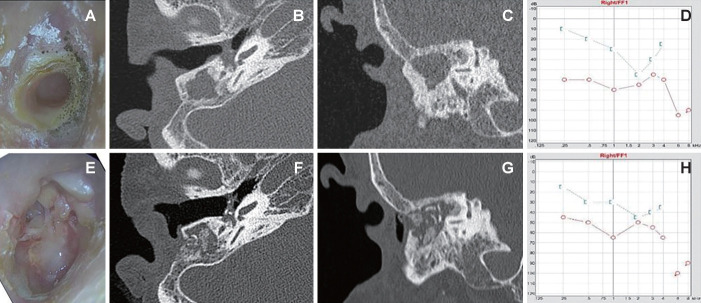

Abstract Image